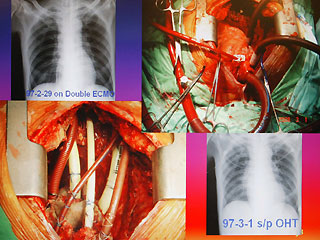

病人陈先生感染细菌性心内膜炎,造成心脏破坏(左下方),进行全心脏摘除术,并放置叶克膜(右上方)体外维生系统以维持生命。